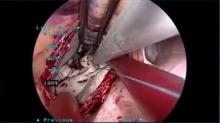

Niv Ad of West Virginia University Heart and Vascular Institute, Morgantown, West Virginia, discusses the benefits of using a fibrillating heart technique in minimally invasive mitral surgery. Dr. Ad illustrates this method using video examples and presents the results.